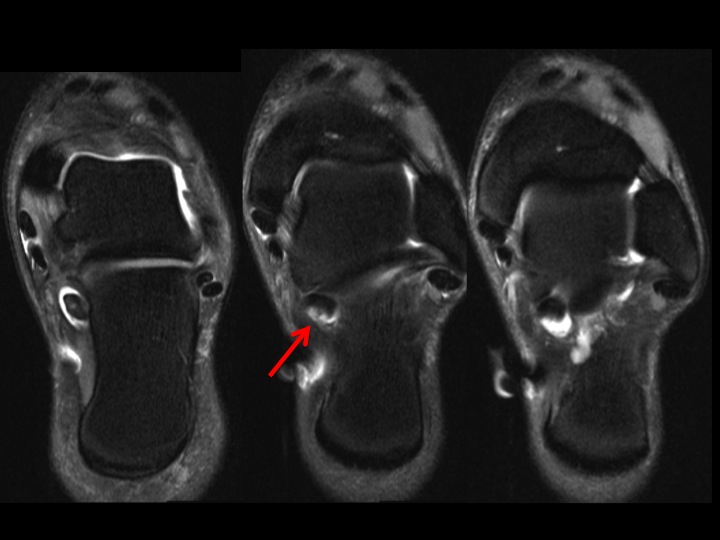

Figure 1 for case FHL partial tear and tenosynovitis

Figure 1

There is a low grade partial tear near the level of the subtalar joint with moderate tenosynovitis. Ive seen relatively few FHL tears, and not in this location.

FHL partial tear and tenosynovitis